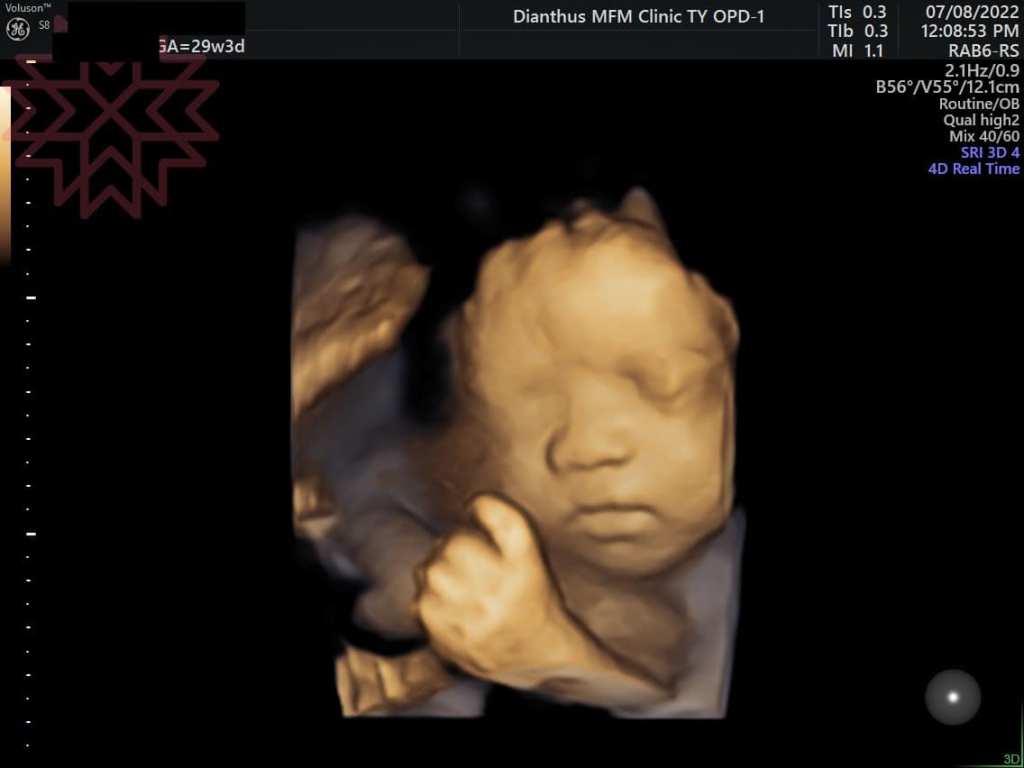

甚至到29週的時候

寶寶的心臟不堪負荷產生心臟衰竭

開始有腹水及胎兒水腫的狀態(如圖)(細節就不說了)